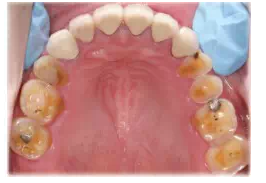

圖18修復完成后的上下頜咬合面觀

圖19患者修復完成后的正面像及牙合曲線